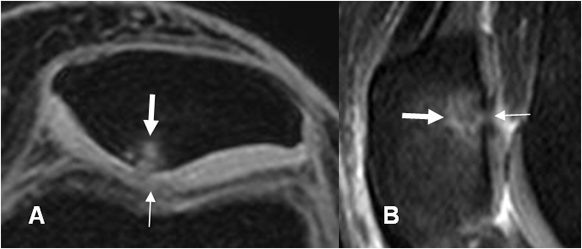

Fig 173. Lesión subcondral.

A: RM 3D axial en T1 STIR y B: RM sagital en STIR. Adelgazamiento del cartílago articular a nivel del vértice, (Flechas delgadas) menor del 50%, con áreas hiperintensas en la patela, que corresponden a lesiones subcondrales. (Flechas gruesas).